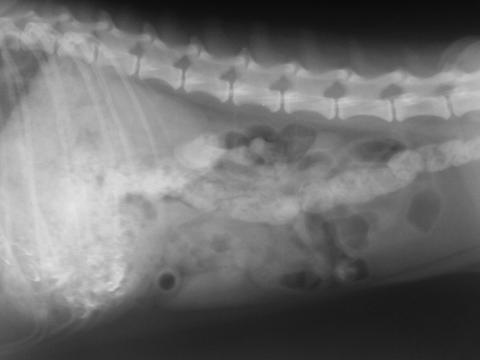

見ればわかると思いますが、画像を拡大できるので背骨を重点的に拡大してみました。

かなり細かく、肉眼では見落としそうな部分まではっきり認識できます。

この機能を使えば、生のレントゲン写真でおかしなところに当たりをつけて、KALOSをつかって細かなところを見るということもできると思います。

はっきり見えないかもしれませんが、拡大したときに横にまっすぐな線が入ります。

これは決して異常ではありません。

レントゲンを撮る際には、グリッド(ブレンデともいいます)といわれるX線の散乱線(臓器や骨に当たってレントゲンビームが飛び散る)を抑えるためのものを取り付けて撮影しています。

通常、肉眼ではわかるのですが、通常のデジカメなどで撮影した場合、グリッド線がつぶれてしまうことが多くあります。

それが、拡大したときに多少のつぶれはありますが、明瞭に写っています。

カメラの解像度がかなりいい証拠になります。